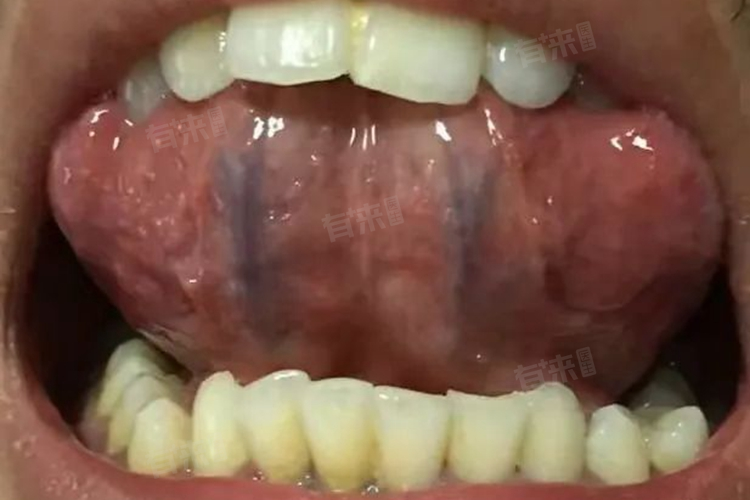

舌下血管发紫发黑可能由多种原因引起,常见的原因主要包括生理因素、色素沉着异常、口腔黏膜炎、创伤后遗症等。

2、色素沉着异常:在舌下区域,如果出现色素沉着过度的情况,则可能导致血管看起来更暗,甚至呈现紫色或黑色。这种情况可能是由于遗传因素、激素水平变化或其他不明原因造成的。

3、口腔黏膜炎:当发生慢性刺激性口炎时,长期的机械性或化学性刺激(如过硬的牙刷、过于辛辣的食物)可以引起舌下区域的炎症反应。这种炎症不仅会引起疼痛和不适感,还可能导致该区域的微循环障碍,造成局部血管扩张和血液淤滞,进而出现紫色或黑色的表现,此情况往往伴随有口腔黏膜的红肿、溃疡等症状。

4、创伤后遗症:无论是意外咬伤、手术后的恢复过程还是其他形式的物理损伤,都可能对舌下的血管结构造成破坏。受伤后,受损的血管可能出现出血、血肿形成等现象,这些都会导致局部颜色加深。

3、雷诺病:是一种以小动脉阵发性痉挛为特征的疾病,主要影响手指和脚趾,但也可能波及到其他末梢部位如舌头下方。疾病发作时,受影响区域的血管会急剧收缩,导致局部缺血,使得皮肤和黏膜颜色变得苍白,随后因血液重新流入而变成紫色或黑色。

此外,血管瘤是一种由异常发育或增生的血管组成的良性肿瘤,它可以发生在身体的任何部位,包括舌下区域,舌下血管瘤可能会导致局部血管颜色发生变化,呈现出紫色甚至黑色。